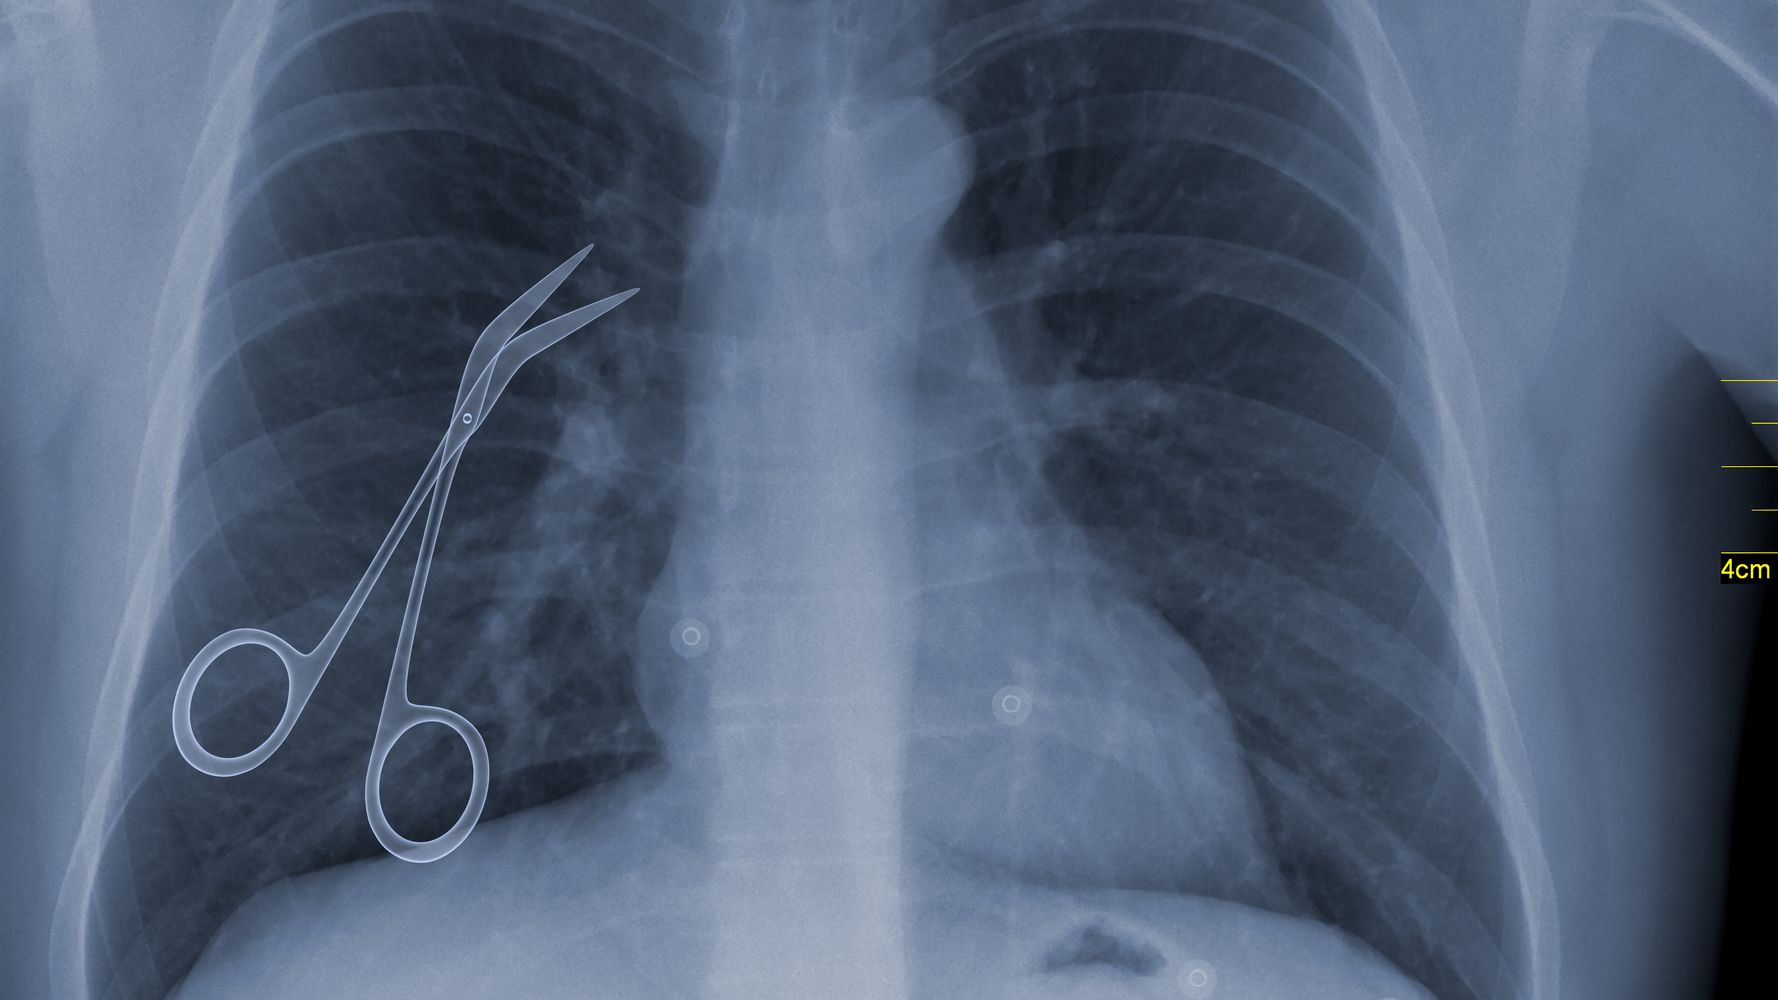

Δυστυχώς, όλες οι προσπάθειες της Bachena ήταν μάταιες, και ο πόνος της έγινε πρόσφατα αφόρητος. Αυτή τη φορά, κατόπιν συμβουλής γιατρού, υποβλήθηκε σε ακτινογραφία άνω-κάτω κοιλίας, η οποία έδειξε ένα χειρουργικό ψαλίδι, που πιθανότατα είχε ξεχαστεί από την επέμβαση αφαίρεσης της χοληδόχου κύστης της, πριν από 20 χρόνια!